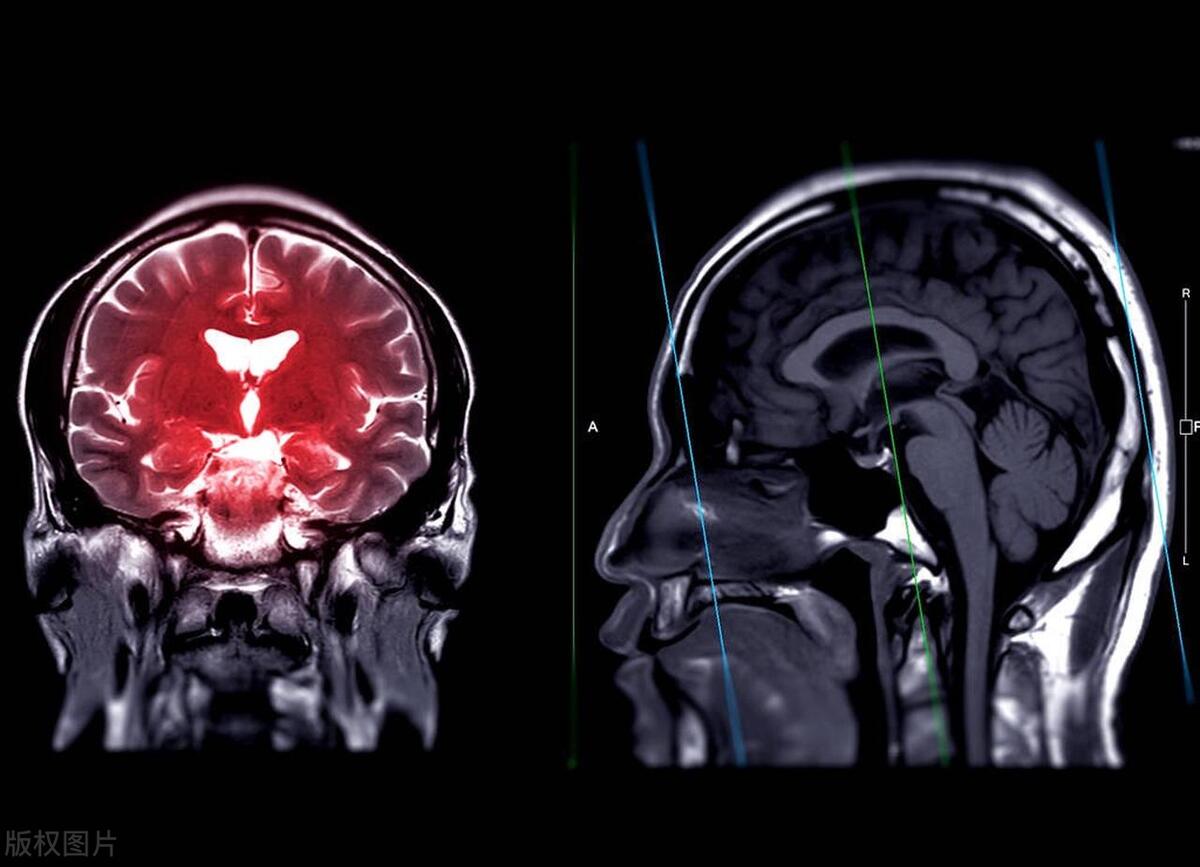

姐姐也有自己的难处。她多次尝试与婆婆沟通,希望她能够减改变饮食习惯,但婆婆总是不听。三年后,不幸降临到了婆婆身上。她突然中风,无法自理,需要长期的照顾。这一消息让我们全家都感到震惊和沮丧。如果婆婆愿意改变自己的饮食习惯,或者尝试使用低钠盐,这种不幸或许可以避免。

脑卒中和心血管疾病是世界范围内的主要健康威胁,造成了数百万人的生命和健康受损。近年来,一项重要的研究表明,食用低钠盐饮食可能是降低脑卒中、心血管疾病和死亡率的有效策略。

1、降低脑卒中风险:研究发现,食用低钠盐饮食的人群脑卒中的风险显著降低。高钠摄入与高血压的紧密关联是导致脑卒中的一个主要机制。通过减少钠盐摄入,可以有效地降低高血压的风险,从而减少脑卒中的发生率。